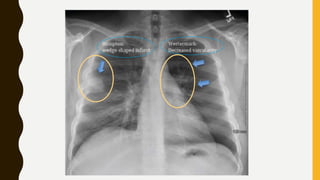

IMAGING

• Chest x-ray is usually normal

Findings, such as

• Focal oligaemia (westermark sign),

• A peripheral wedge-shaped opacity, usually in the

lower half of the lung field (hampton’s hump), or

• An enlarged right descending pulmonary artery

(Pallas’s sign) are rare